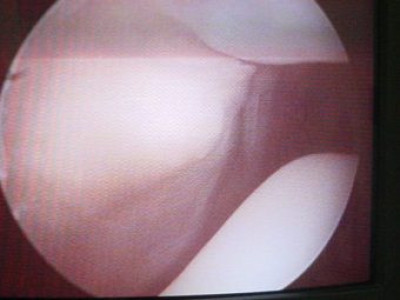

Luxación Habitual de Rótula

Envíado por Dr. Eduardo E. Martínez Melara